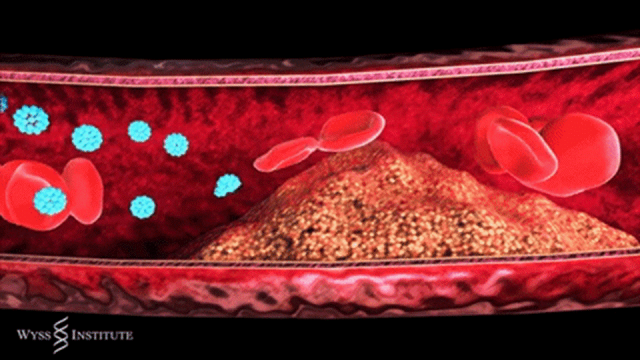

简单来说,动脉粥样硬化是血管壁的一场 “慢性病变”:血液中的脂质在血管壁沉积,伴随炎症反应不断发展,逐渐形成斑块。这些斑块会像 “水垢” 一样堵塞血管,让血流变慢,严重时甚至完全阻断血流,引发致命问题。

近年来,越来越多研究证实,干细胞对于修复血管内皮,促进血管新生,以及通过调控炎症对动脉粥样硬化产生的作用。

间充质干细胞可以分化为内皮细胞,加速受损内皮修复,抑制动脉狭窄的形成。另外,体外输注的间充质干细胞能够向受损部位募集,并进一步分化为内皮细胞,修复损伤血管。